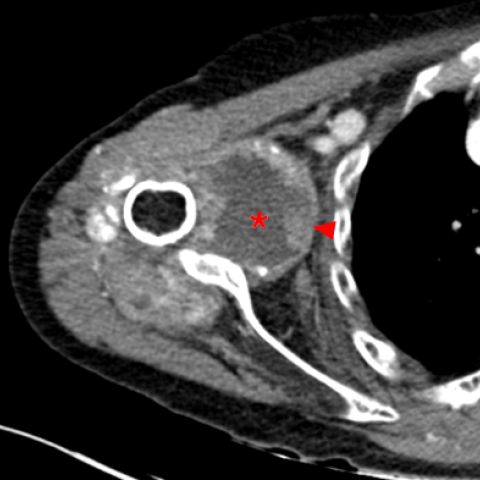

CT多平面重建软组织窗显示关节腔内存在大量积液(*),并伴有广泛的滑膜增生(箭头)。肩袖肌肉尤其是肩胛下肌明显脂肪浸润(五角星)。